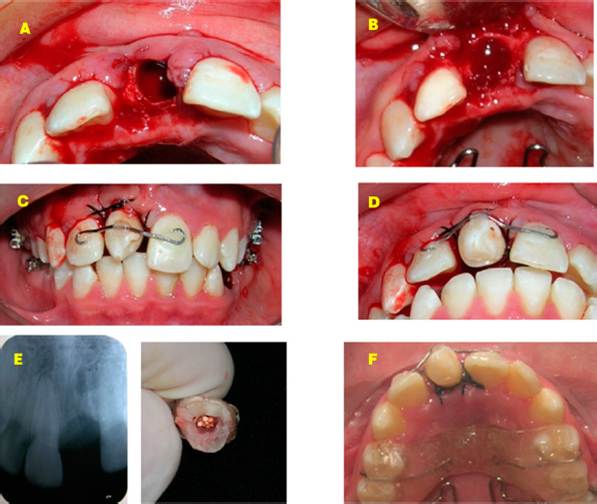

In the first phase of treatment, bands were placed on the upper first molars, an anchorage device was used, and the bite was lifted with an acrylic plate to avoid occlusal contact. Subsequently, the upper right central incisor was extracted, following the protocol for the extraction of the lower left first premolar, preparation of the surgical site, and the process of dental transplantation and splinting for four weeks (Figure 3). In the second phase, GAC© prescription Roth 0.022” Ovation brackets were placed. They were first placed in the lower arch to reduce the inclination of the incisors and improve the position of the teeth while the repair and healing of the peri-implant tissue of the auto-transplanted tooth was being performed (Figure 4).

Figure 3 First phase of treatment. A-B. Preparation of the receptor niche. C-D. Fixation of the transplanted tooth in the maxillary central site. E. Post-extraction dentoalveolar radiograph. F. Use of the acrylic plate to promote bite opening.